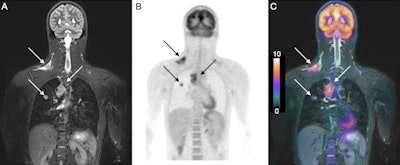

In regard to staging, FDG-PET/CT detected 141 positive nodules (20%) from the 696 sites anomalies, compared with FDG-PET/MRI, which discovered 135 true-positive sites (19%). In addition, FDG-PET/CT reported 560 true-negative results (80%), compared with 551 true-negative findings (79%) for FDG-PET/MRI. The results proved to have no statistically significant difference.

As for response assessment, FDG-PET/CT spotted six true positives (0.9%), which would indicate an incomplete treatment outcome, among a total of 609 disease sites. By comparison, FDG-PET/MRI detected five of those six true positives (0.8%), with one incomplete treatment response missed due to a "perceptual error." When the researchers corrected for that miscue, they achieved "perfect agreement" for staging and "excellent response assessment agreement" between FDG-PET/MRI and FDG-PET/CT, they added. Again, there was no statistically significant difference.